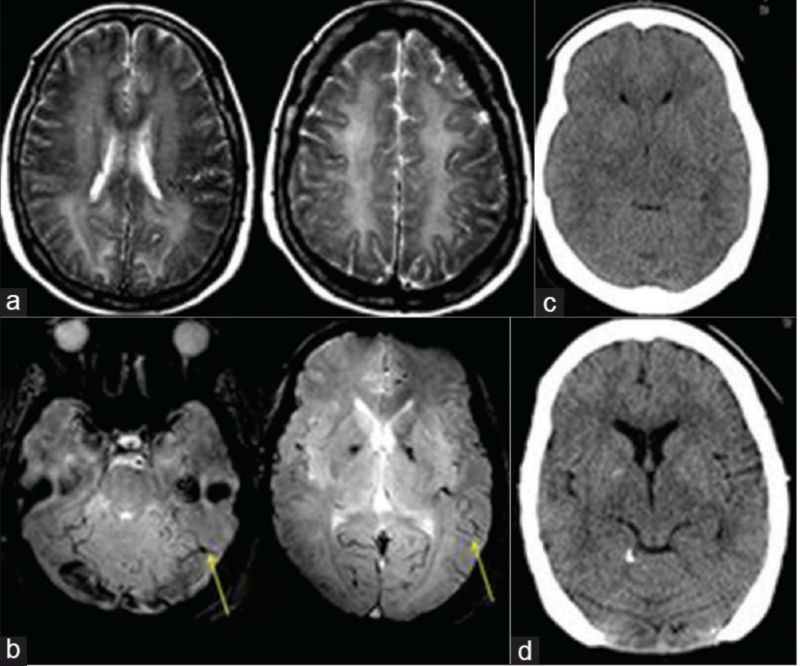

52岁,男性,头晕20余天,伴言语不利、智能下降。患者自述于20余天前无明显诱因下出现头晕,呈持续性头重脚轻感,无明显规律,伴有言语欠流利、智能下降,表现为计算力、理解力、记忆力下降,偶有咳嗽、呈阵发性单声咳,咳少许白色粘痰;间断发热,最高体温38.5℃。影像学如下:

影像学可见双侧颞、顶叶及右侧额叶多发散在皮层下白质病变,长T2,DWI高信号,ADC高信号。疾控中心HIV-1抗体:阳性,CD4+64cell/ul。

诊断: HIV相关脑病(HIV相关痴呆)

根据当前针对HIV相关神经认知障碍(HIV-associated neurocognitive disorder,HAND)的国际“Frascati”分类标准,可分为无症状性(ANI),轻度认知障碍(MND)和HIV痴呆(HAD)三个阶段。ANI为量表提示有认知域损害,但日常生活能力无影响;MND轻度的认知功能障碍且影响日常生活能力轻度受损;HAD为明显认知障碍且日常生活能力明显受损。(Neurology. 2007 Oct 30; 69(18):1789-99.)

艾滋病相关性痴呆在 20% 的 AIDS患者中发生,往往是HIV感染缓慢进展数月后出现的迟发表现,这类患者CD4+细胞>350/μl。

HIV相关痴呆与 “皮质型”痴呆如阿尔茨海默不同,前者较少出现失写、失算、失用等皮质功能障碍。一些研究者称其为皮质下痴呆,表现为短期记忆和执行功能损伤。

脑部 MRI 显示萎缩和广泛白质改变。运动障碍也可单独发生或伴随 HIV引起的痴呆一同发生发展。HIV 感染者中运动障碍的发生率为 3%。

其影像学表现常位于白质,如脑室旁、半卵圆中心,呈对称、弥漫、云雾样白质异常,病灶可延伸至灰白质交界处。

看两例文献图:

Case1:

Case2:

图自:Topics in Magnetic Resonance Imaging .Volume 23, Number 5, October 2014

回到该病例,无论临床及影像学,除需要进一步完善认知功能评估之外,尚需要与进行性多灶性白质脑病(PML)相鉴别。PML是由JC病毒侵犯免疫抑制的HIV患者导致的中枢神经系统感染。影像学特点是以顶叶为主的皮层下白质散在受累,并呈融合趋势,会累及U形纤维是其特点之一。